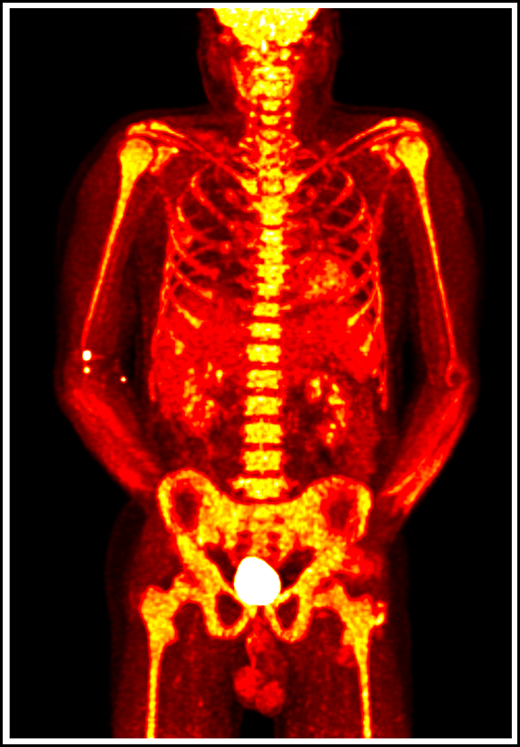

18F-fluorodeoxyglucose positron emission tomography in a patient with VEXAS syndrome demonstrating hypermetabolic activity in bone marrow (yellow). Somatic mutations in UBA1 in hematopoietic cells lead to myeloid-driven inflammation that is often refractory to treatment in patients with VEXAS syndrome.

VEXAS is a severe, progressive disease with clinical features that bridge rheumatologic and hematologic conditions. Systemic inflammation involving the skin, lungs, blood vessels, and cartilage often leads to the assignment of various clinical diagnoses, including Sweet syndrome, relapsing polychondritis, polyarteritis nodosa, and giant cell arteritis. Additionally, patients with VEXAS suffer from a spectrum of hematologic problems, including macrocytic anemia, thrombocytopenia, thromboembolic disease, and progressive bone marrow failure, which can evolve to hematologic malignancy (Figure 1). An increased risk for hematologic malignancy, most notably myelodysplastic syndrome (MDS), has been reported in many rheumatologic diseases, and conversely, MDS has been associated with a variety of autoimmune syndromes.4-8 VEXAS syndrome may explain some of these historic clinical associations.